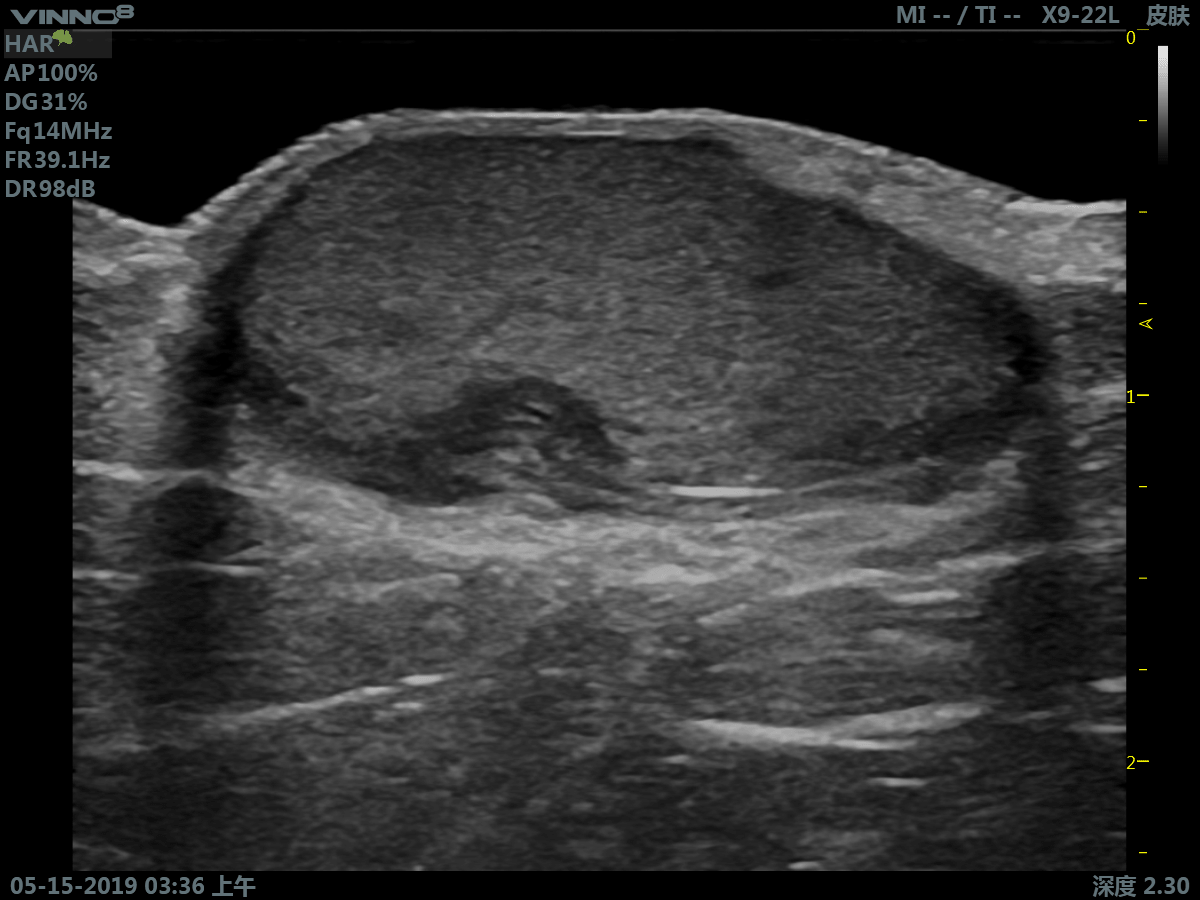

Портативный ультразвуковой сканер VINNO 8

Преимущества портативного УЗИ аппарата VINNO 8

- инновационная платформа RF обеспечивает суперчистое изображение в результате сверхвысокой скорости обработки данных

- сверхвысокая частота (до 23 МГц на линейном датчике)

Клиническое применение:

- мелкие объекты (включая щитовидную железу, молочную железу, семенники и т.д.)

3. Режим тканевой гармоники - технология выделения гармонической составляющей колебаний внутренних органов, вызванных прохождением сквозь тело базового ультразвукового импульса.